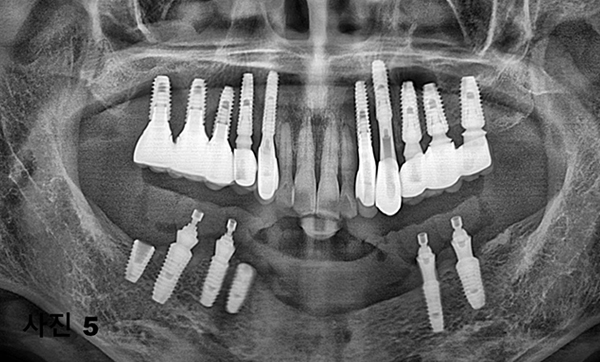

5개월후에 영구적인 티타늄과 지르코니아 보철물이 구강내 장착된 (사진5)와 x-ray(사진 6)모습이다.